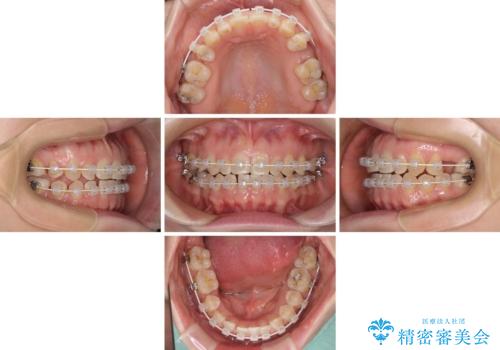

隙間の空いた歯列とボロボロの乳歯 インプラント治療と矯正治療

- 隙間の多い歯列や傾斜した奥歯、むし歯の酷い残存乳歯を気にして来院された患者様です。

歯列はワイヤー矯正にて改善することとしましたが、上下歯列にも隙間があったので、舌の突出癖を改善するトレーニングを徹底的に行うこととしました。

傾斜した下顎の奥歯は、矯正治療にてまずは歯軸を改善させ、隙間が閉じられるようであればそのままに、閉じられないようであればインプラント治療を行うこととしました。

上顎のむし歯の酷い残存乳歯は抜歯をし、矯正治療の途中でインプラントを埋入、矯正治療後に補綴治療を行うこととしました。

舌の突出癖改善のトレーニングが全くうまくできず、治療期間が長期化しました。

早く治療を終えたいとの要望があり、トレーニング次第と伝えるとようやく練習をするようになり、その後は速やかに上下の隙間が改善されました。